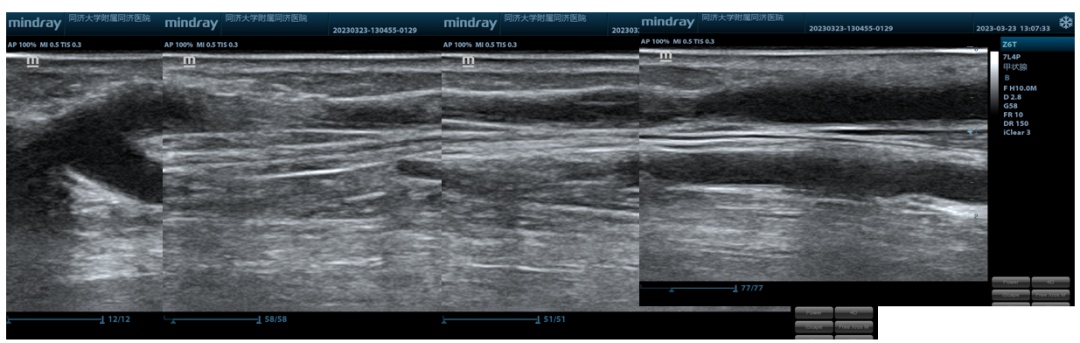

术前血流量

该患者已行过两次介入PTA治疗,上一次干预3个月再出现内瘘血流量明显不足,几乎无震颤,经检查发现为流出道血管内膜增生明显,需要再次干预。通常血管内膜增生明显的血管通路病变,对于单纯应用球囊扩张干预的长期通畅率效果并不理想,而抛弃这段血管重建,对于武先生自身血管条件而言则意味着可能需要临时插管以及面临术后穿刺困难的问题。

经过科室内讨论后,根据目前共识及临床试验证据,对于这种静脉血管内膜增生病变建议可以使用药涂球囊干预延长通畅时间,本次结合近心端正常静脉内径,选择了合适型号的新型高压药涂球囊进行扩张治疗。